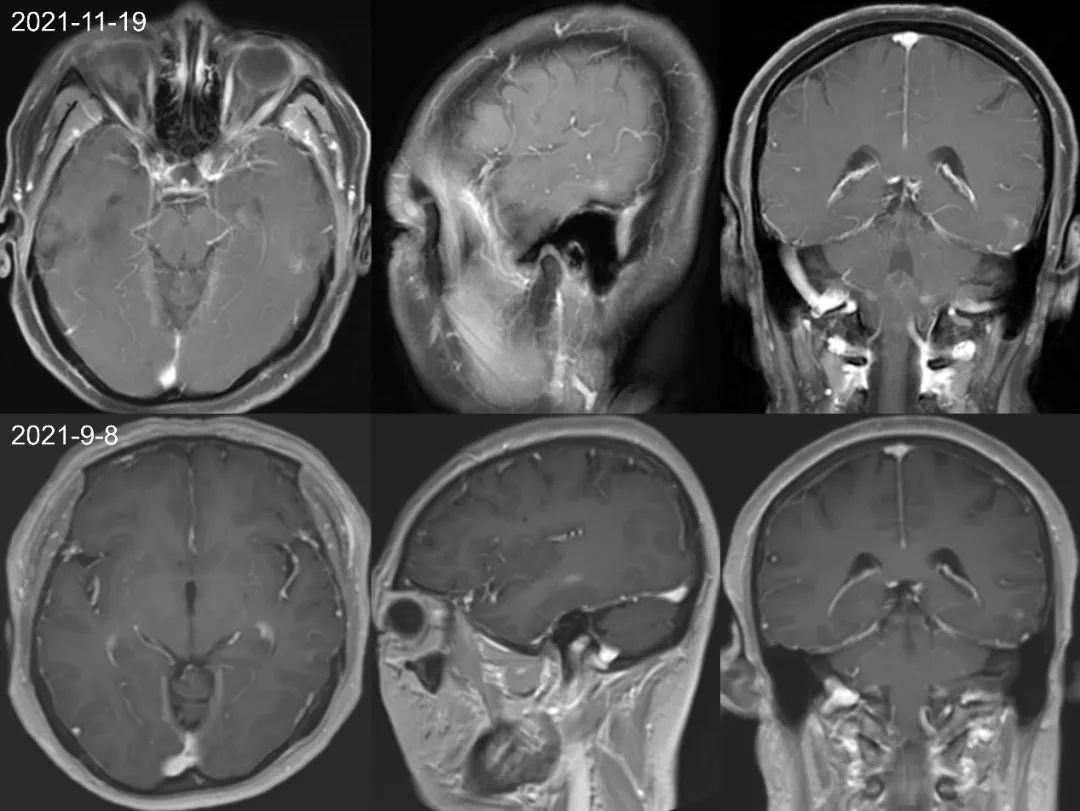

首次检查 2021-1-5 日发现左侧颞叶强化结节,轴矢冠状位都能看到,但是平扫看不到,周围亦未见水肿信号,此时没经验的诊断医生估计会考虑为转移瘤,一直困扰着患者和临床医生。但是在其余 7 次检查中 2021-3-2 至 2022-6-22 一年半多的时间,左侧颞叶强化结节仍然存在,并且基本没啥变化,如果是转移瘤会这么长时间无任何干预都处于一个静止状态吗?,此时是不是需要考虑其他的诊断?,究竟是什么呢,有经验的医生肯定会想到:是毛细血管扩张症。

仔细观察本例左侧颞叶强化结节,中心为明显强化,周围为稍淡淡样的强化,此为毛细血管扩张症的特点。